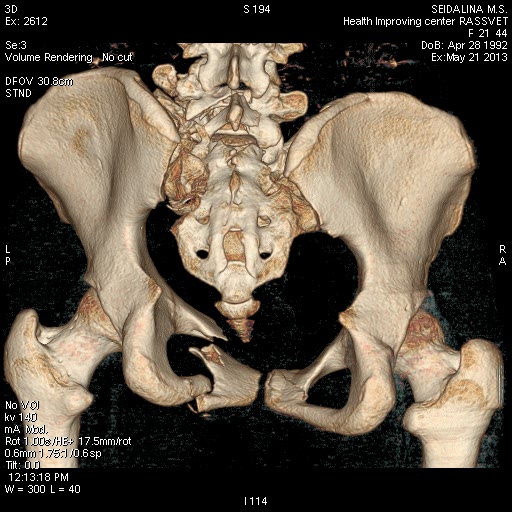

КТ до операции.